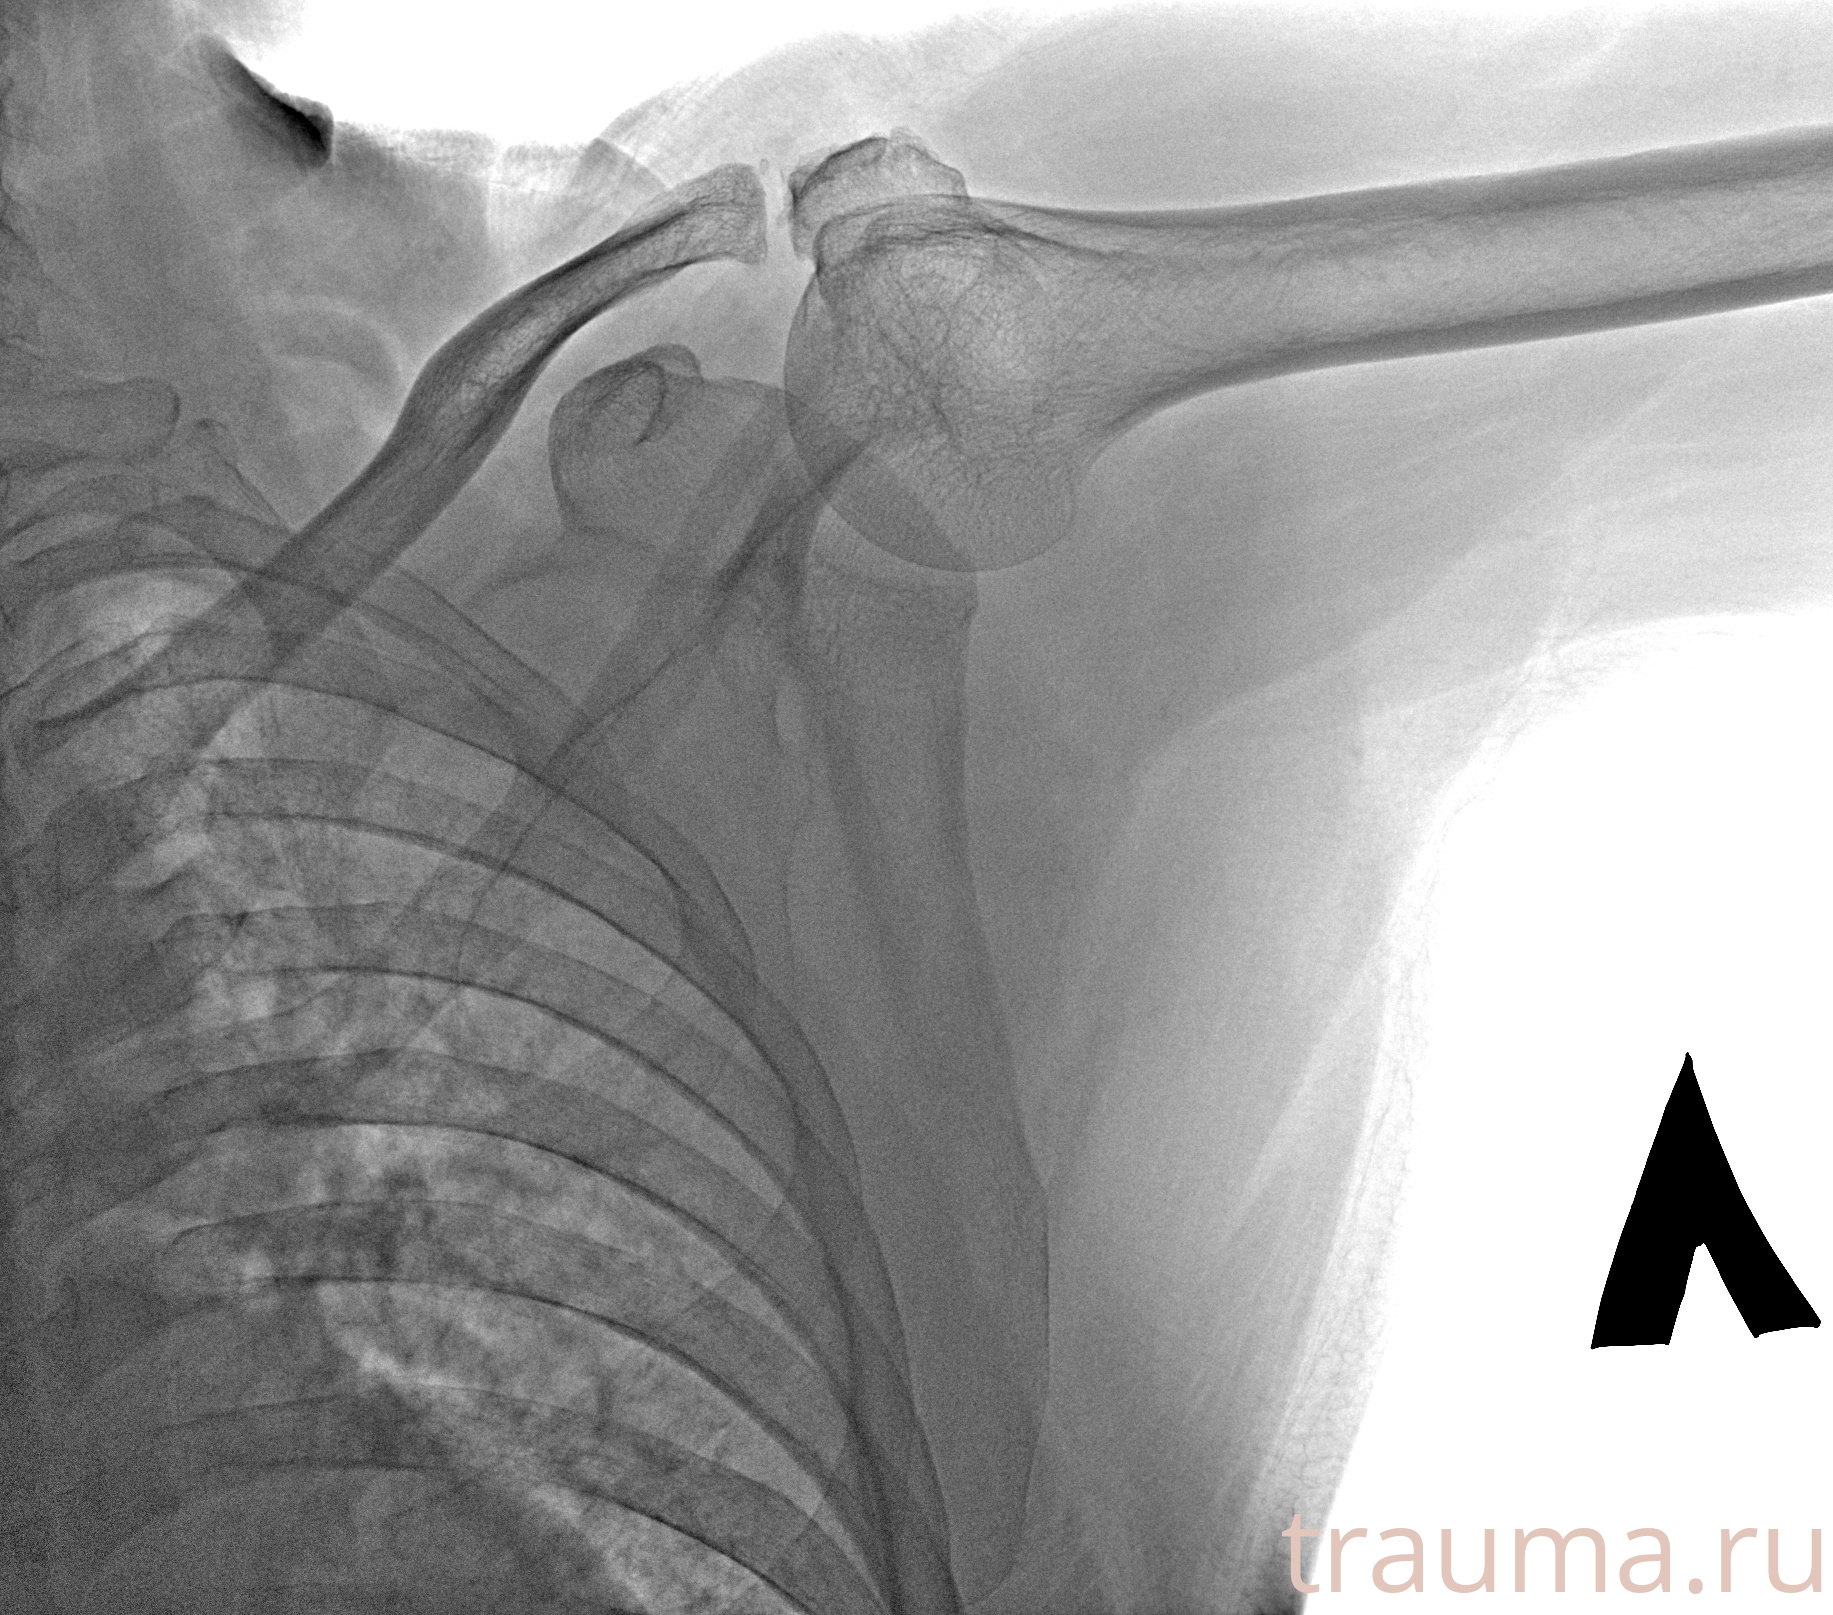

Рентгенограммы

Рентген на дому: по вашему адресу приезжает врач-рентгенолог, травматолог-ортопед с мобильным рентгеновским аппаратом, проводит диагностику травмы или заболевания, делает необходимые рентгенограммы, дает рекомендации по дальнейшему лечению. Получить качественные снимки в домашних условиях возможно благодаря уникальной методике, разработанной МосРентген Центром для института  Склифосовского